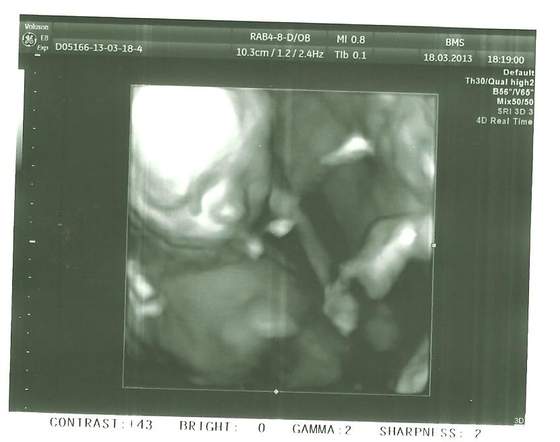

ale czadowo 2 w 1 :-) no no szczęściara miec od razu parkę gratuluje!!!Zobacz załącznik 546271Zobacz załącznik 546272A to moje maluszki:-)pierwsze to chłopczyk a na drugim dziewuszka:-)